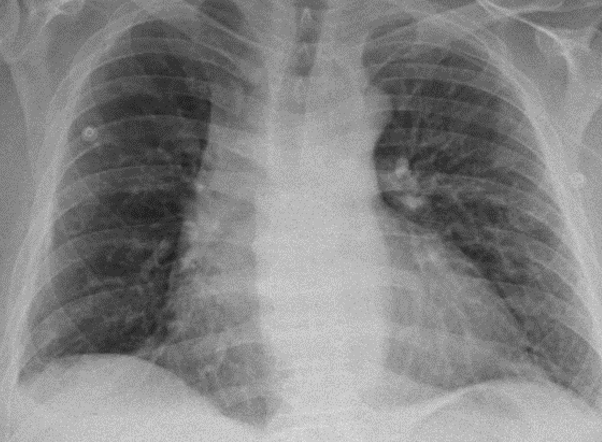

Diagnostic Testing. The patient’s chest x-ray (CXR; Figure 1) and computed tomography angiography (CTA; Figure 2) confirmed the presence of diffuse infiltrates across both lungs, and mediastinal and perihilar adenopathy.

Fig. 1. Portable CXR illustrating areas of diffuse pulmonary infiltration (yellow arrows).

Previous CXR from the patients’ past hospitalizations indicated no previous pulmonary infiltration. Further laboratory studies revealed a white blood cell count of 13,700/µL (normal range: 4500 - 11,000/ µL) with an eosinophilic predominance of 9.8% (normal range: 1-4%).